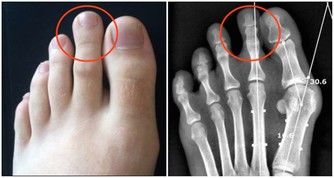

我們的手臂中含有多條動脈和靜脈。如果是深層的靜脈組織出現血凝塊,那麼會導致手臂皮膚發紅腫脹,還會伴有劇烈的疼痛感,這種病情在醫學上稱之為深靜脈血栓形成。

動脈栓塞是指血栓或血管中的異物阻礙了動脈血液流通,當栓塞到達手臂動脈時,

通常會引起手臂皮膚變色、手指冰冷異常,患者還會感覺上肢無力,或是直接喪失手臂的運動能力。

肌肉症狀另一方面,不論是靜脈還動脈中存有血栓,手臂肌肉都會明顯受到影響。

常見的包括肌肉痙攣、手臂酸痛無力、上肢麻木等。